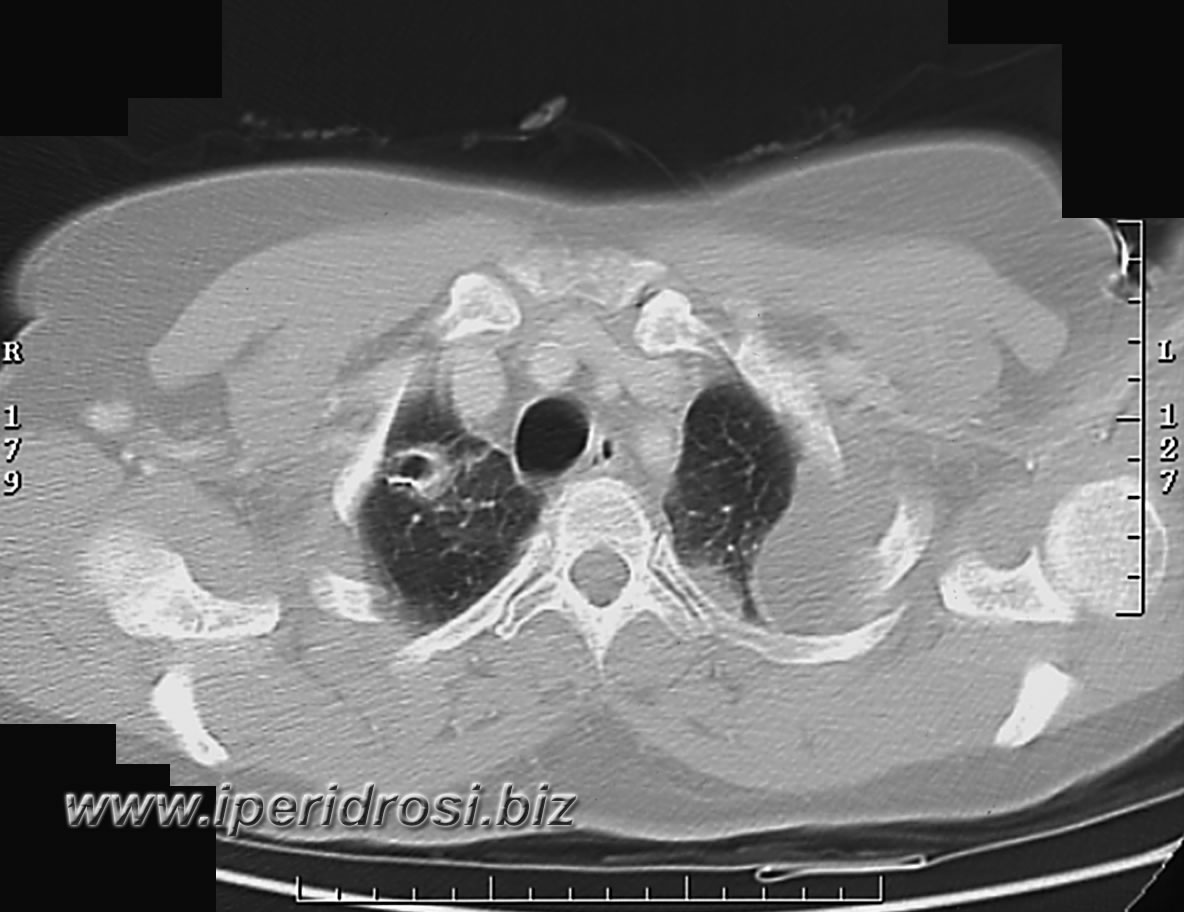

Torace: a sinistra abbondante versamento pleurico e parzialmente saccato, atelettasia parenchimale basale bilaterale più evidente a sinistra dove residua limitato parenchima ventilato.